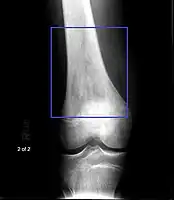

Osteosarcoma of the distal femur -